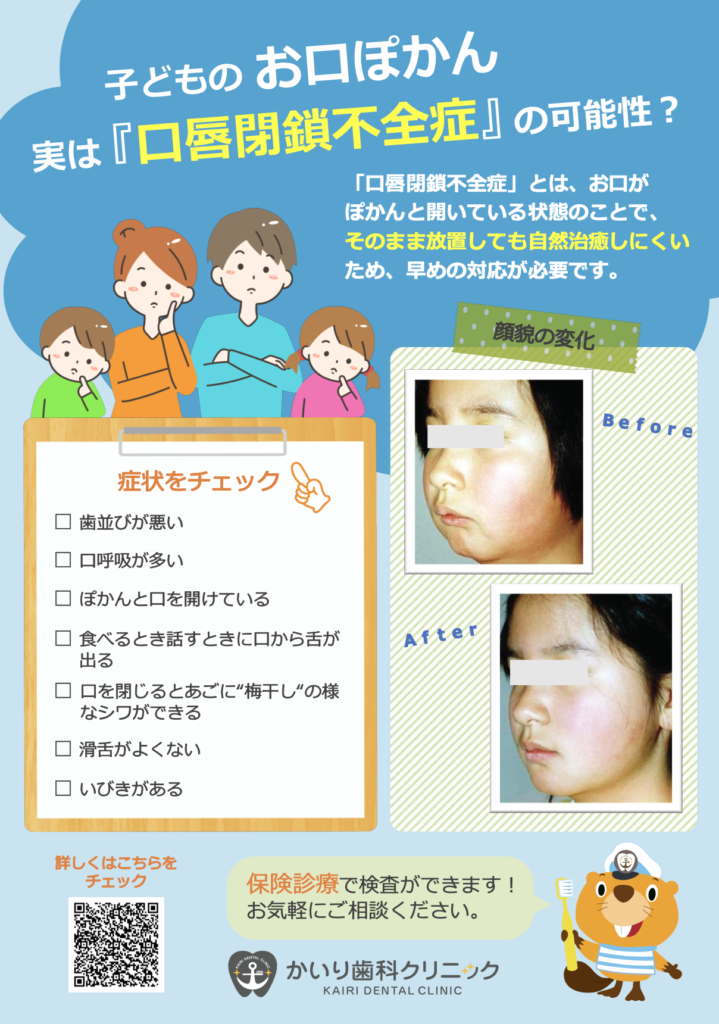

子どもの歯並び予防のMFT①〜おくちポカーンのトレーニング(口輪筋)〜

2024.06.05

☆おくちポカーンのトレーニング(口輪筋)のトレーニングのご紹介☆

今回は①〜③のお口を閉じる力が弱いことが原因の一つである

『口唇閉鎖力不全症』〜何もしていない時(安静時)にお口が開いている状態〜

上記のように、お口を開いていることで、虫歯や歯肉炎や歯並びなどのお口の問題だけでなく、アレルギーやアデノイドの肥大など様々な疾患を重症化させるリスクとなります。

つまり、お口をきちんと閉じるようにできるようになれば、口呼吸、鼻へい、気道閉塞、アレルギーなどを軽症化できる可能性もございます。

当院では、お口を閉じる力を測定し(口唇閉鎖力測定)、適応となるお子様に以下のトレーニングを指導しております。